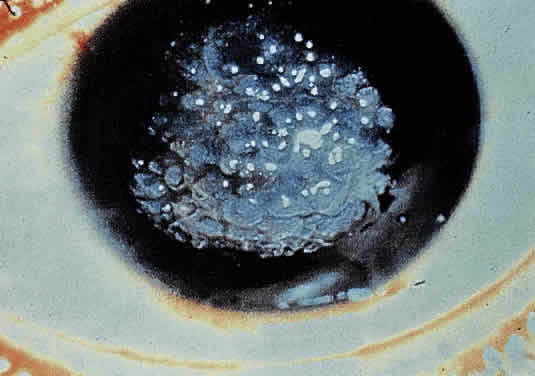

OCULAR FINDINGS. Corneal lesions usually appear early in life, but later onset also occurs.12,15,16 Tearing, photophobia, and painful eyes are common. Pseudodendritic corneal erosions may involve the epithelium alone or may include Bowman's layer and anterior stroma. Central corneal ulcers with bases containing debris described as purulent and as thick and cheesy have been mentioned. All cultures are negative. Multiple intraepithelial opacities may be present and may be linear or arranged in a stellate pattern in the central cornea.17

Other ocular findings include whitish conjunctiva, discrete conjunctival plaques, and papillary hypertrophy. Rats fed a diet containing excessive L-tyrosine develop a disease mimicking human corneal disease.18 The corneal lesions in tyrosine-fed rats appear to be caused by the formation and growth of needle-shaped crystals within epithelial cells.19

A current pathogenetic hypothesis involves crystal production in the cornea as a result of a supersaturated state. When crystal formation is initiated in the central cornea, the disruption of cells forms biomicroscopically evident snowflake-like lesions. The crystals exert a force powerful enough to pierce cell membranes and displace nuclei. Lysosomal enzyme release, polymorphonuclear migration, vascularization, and subsequent healing20 follow cell rupture.

DIFFERENTIAL DIAGNOSIS. The eye lesions may suggest herpes simplex or other types of epithelial infections, developmental anomalies, vitamin deficiencies, or metabolic or storage diseases. The skin lesions are reminiscent of epidermolysis bullosa, dyskeratosis congenita, or keratosis palmaris et plantaris. However, the combination of eye and skin lesions in this pediatric age group is diagnostic. In the past, patients have been treated extensively for herpes simplex keratitis before a proper diagnosis was established. Clinical features helpful in distinguishing tyrosinemia from herpes simplex keratitis include bilaterally stellate, plaquelike lesions that lack club-shaped edges; minimal staining with rose bengal and fluorescein; and a lack of response to topical antiviral therapy.15,16,22